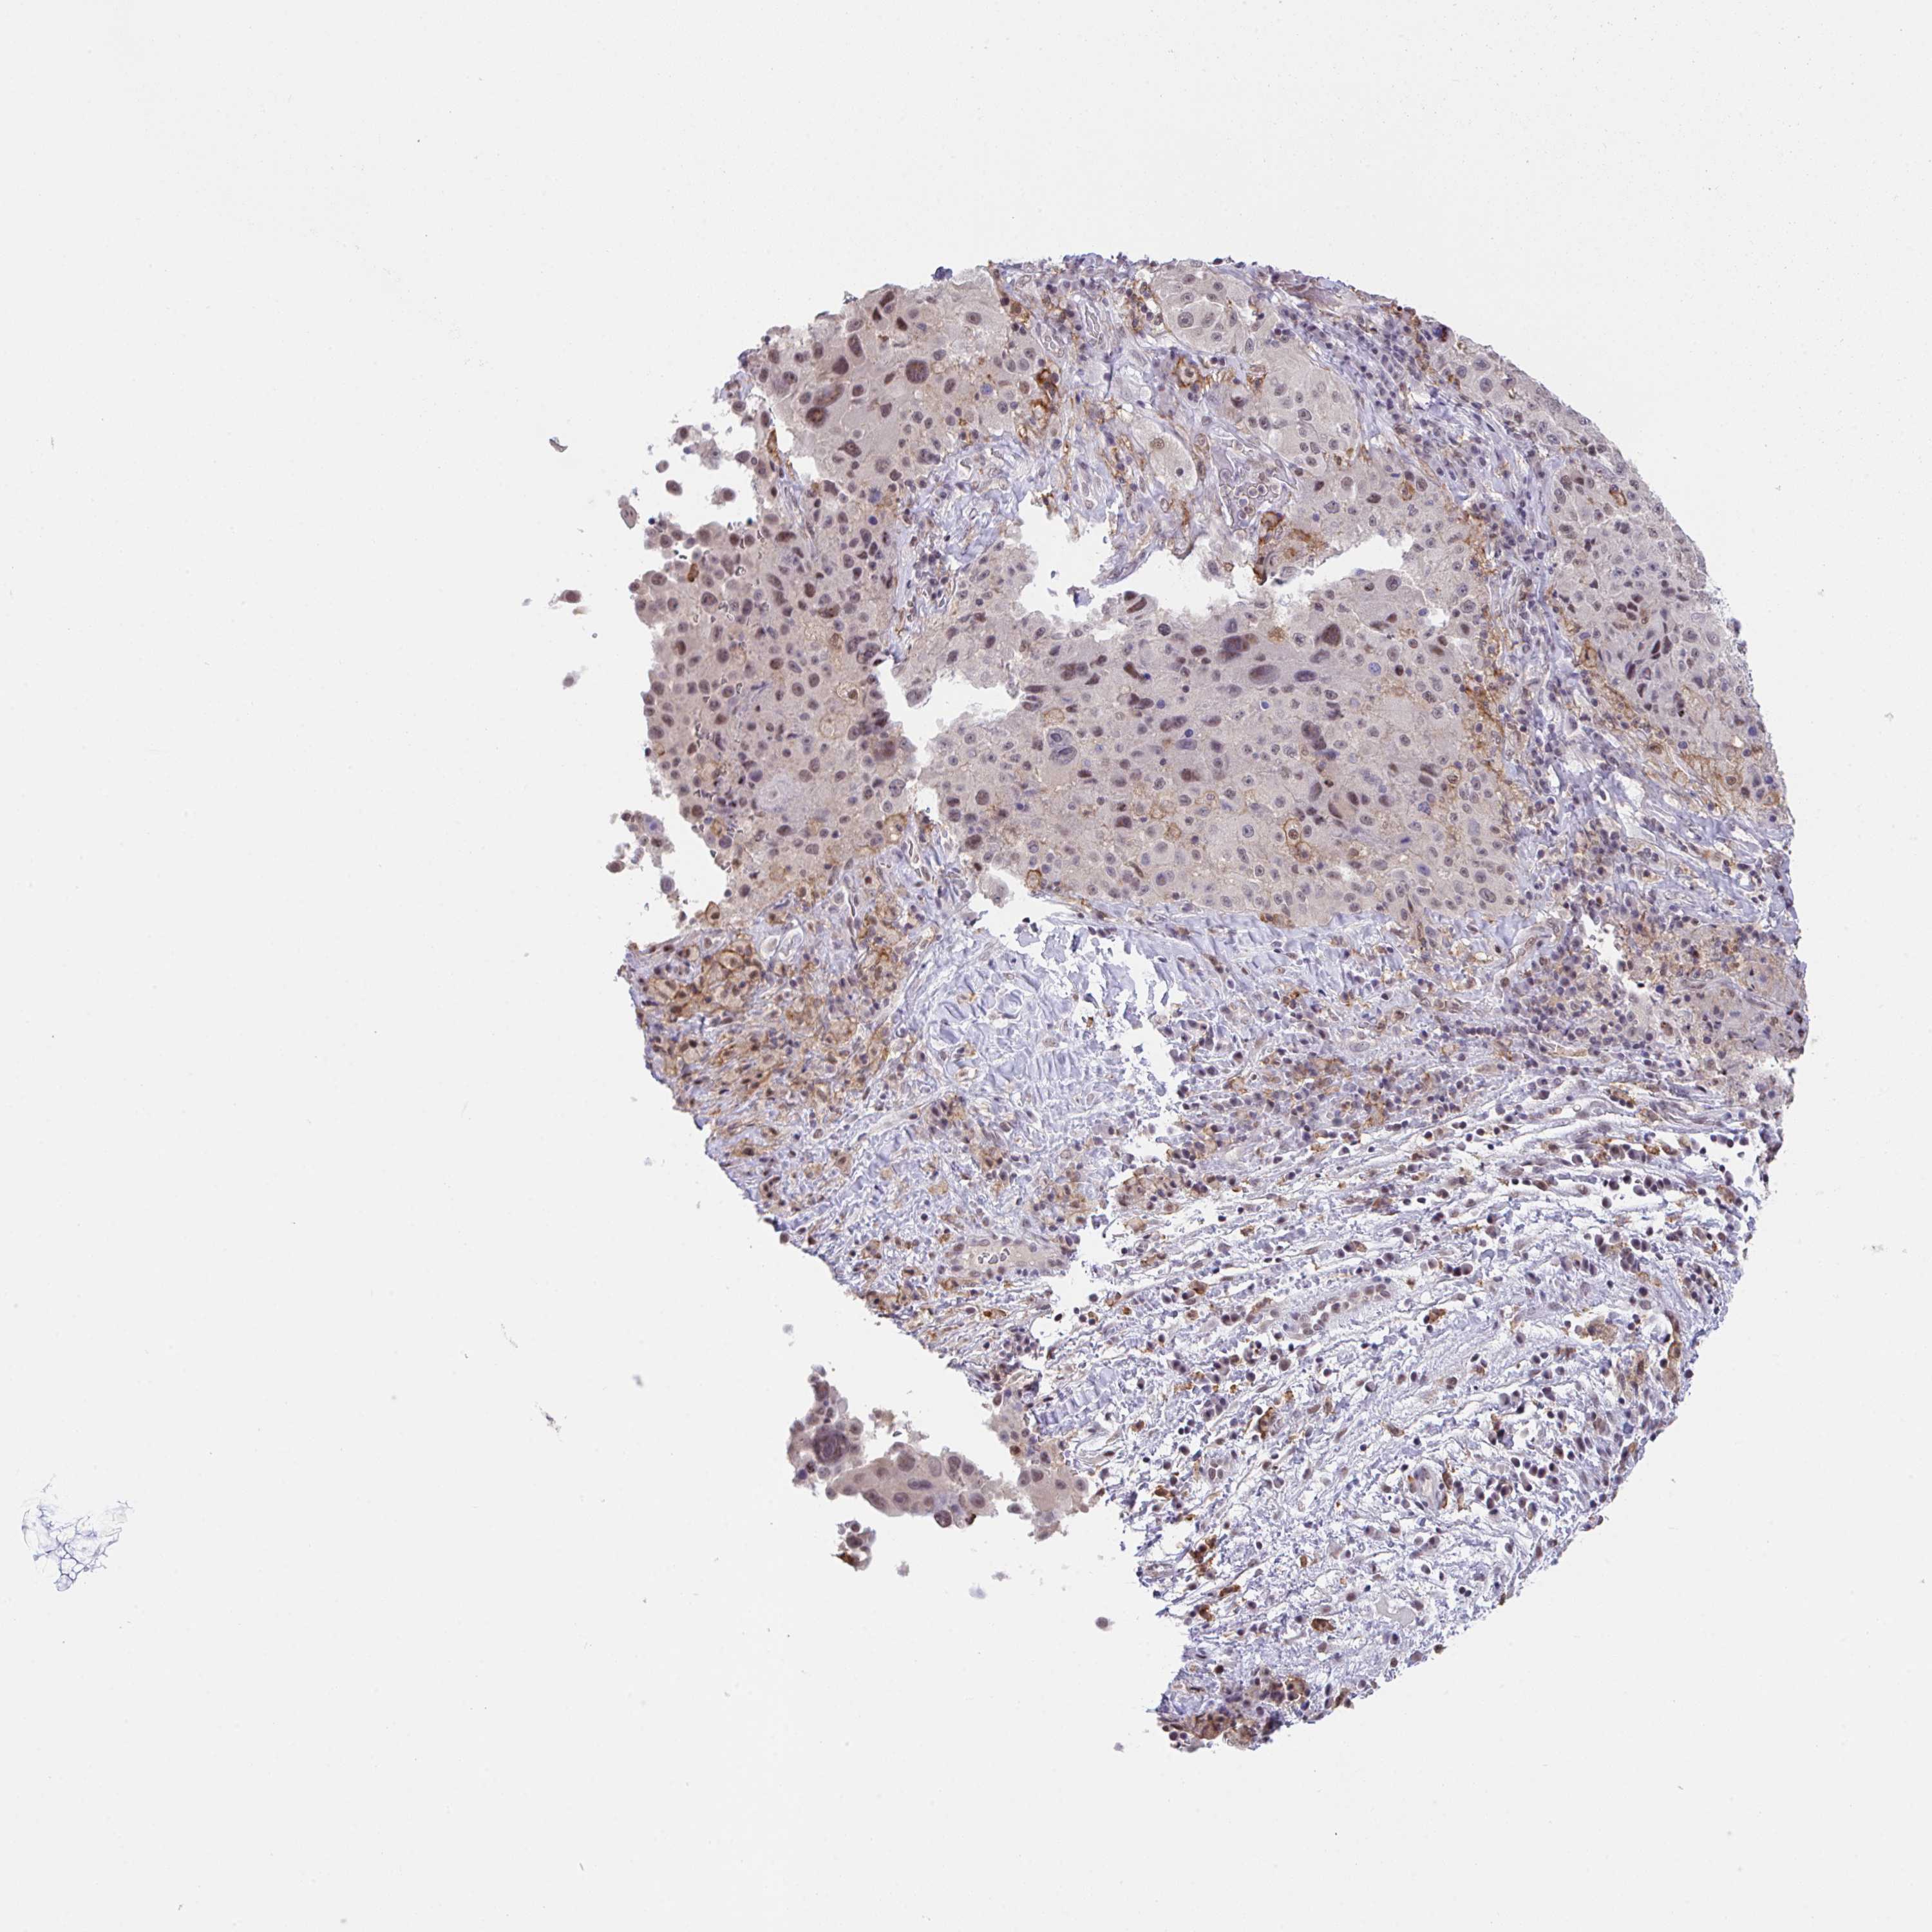

MELANOMA - Protein expressioni

A mouse-over function shows sample information and annotation data. Click on an image to view it in a full screen mode. Samples can be filtered based on level of antibody staining by selecting one or several of the following categories: high, medium, low and not detected. The assay and annotation is described here.

Note that samples used for immunohistochemistry by the Human Protein Atlas do not correspond to samples in the TCGA dataset.

Antibody stainingi

Antibody staining in the annotated cell types in the current human tissue is reported as not detected, low, medium, or high, based on conventional immunohistochemistry profiling in selected tissues. This score is based on the combination of the staining intensity and fraction of stained cells.

Each image is clickable and will lead to virtual microscopy that enables deeper exploration of all samples and also displays staining intensity scores, fraction scores and subcellular localization as well as patient and tissue information for each sample.

Antibody HPA055949

Staining

High

Medium

Low

Not detected

Intensity

Strong

Moderate

Weak

Negative

Quantity

>75%

75%-25%

<25%

None

Location

Nuclear

Cytoplasmic/membranous

Cytoplasmic/membranous,nuclear

Malignant melanoma, NOS

Malignant melanoma, Metastatic site